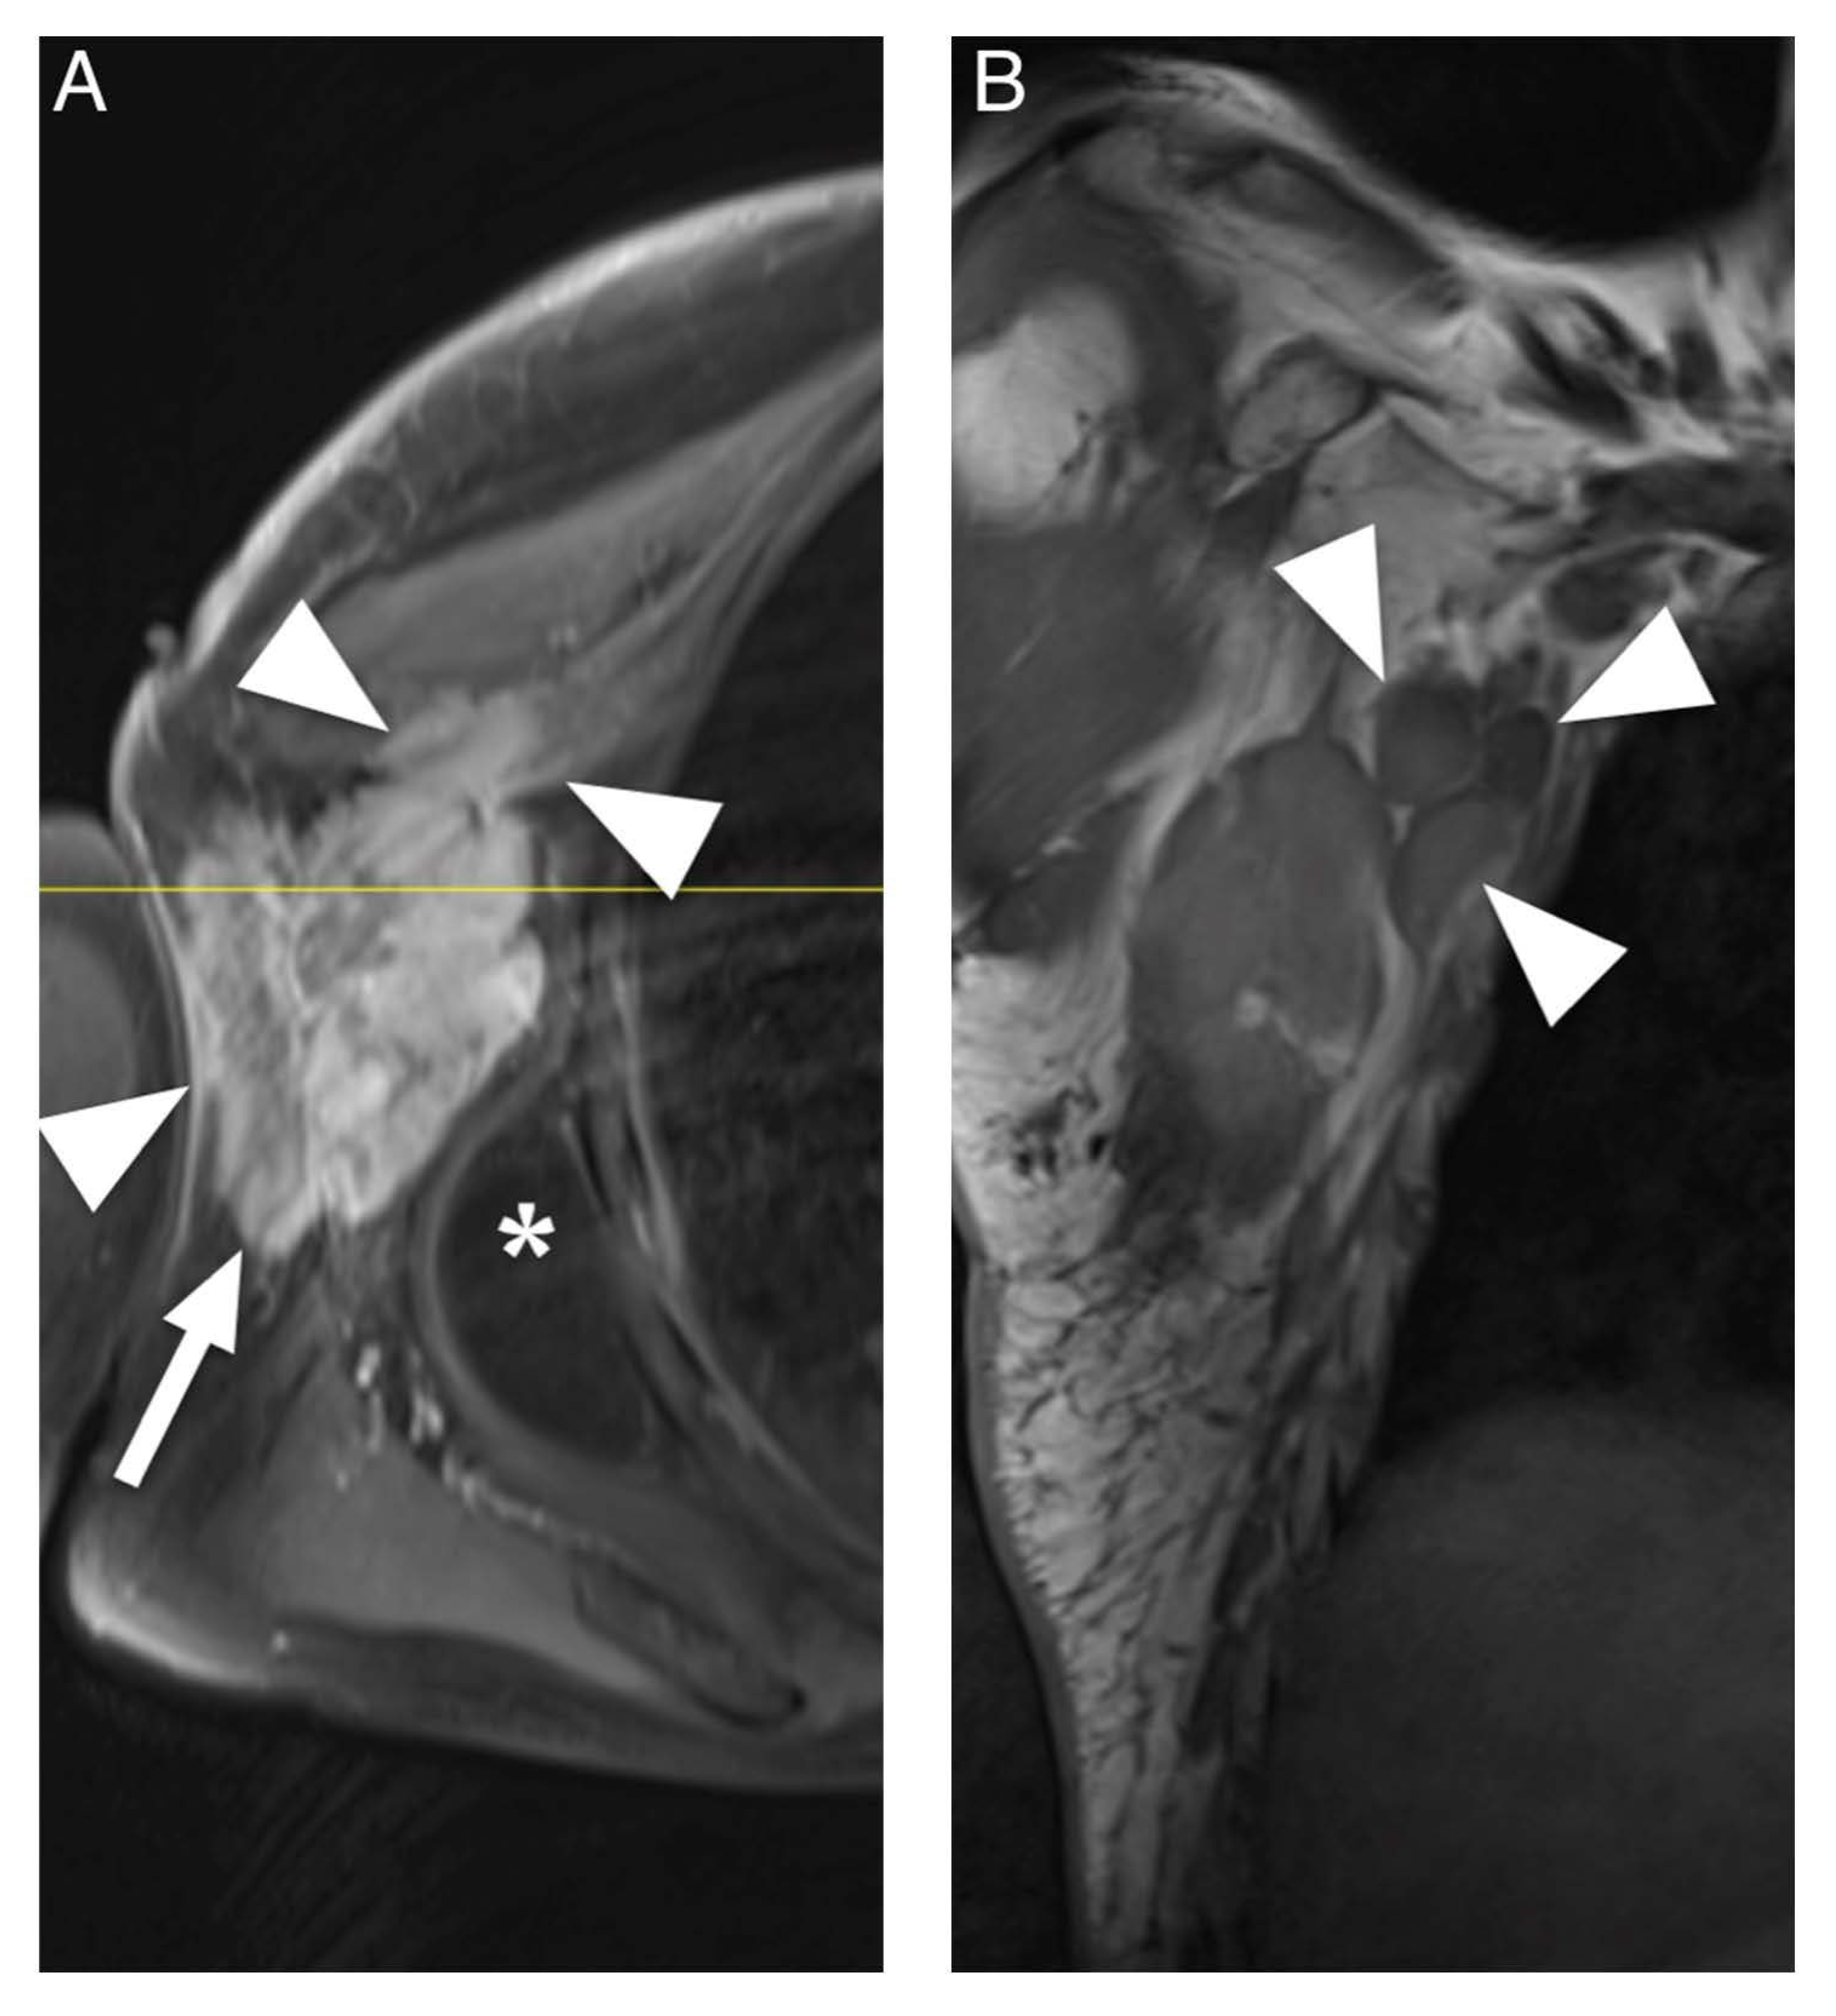

Figure 4.

MRI of a 67-year-old man presenting with a predominantly subcutaneous manifestation of non-Hodgkin lymphoma in the right axilla. (A). Transversal contrast enhanced fat-saturated T1-weighted image shows a lobulated tumor (arrow) with inhomogeneous enhancement pattern which infiltrates into the pectoralis major and minor muscles and skin (arrowheads). Moreover, an accompanying lipoma can be noted (asterisk). (B). Coronal T1-weighted image shows associated lymphadenopathy (arrowheads).

The aim of this systematic review was to identify characteristic clinical and MRI features of appendicular soft tissue lymphoma as currently described in the literature. Diffuse large B-cell lymphoma was the most commonly reported histological subtype and is also the most common type of lymphoma [36]. Clinically, ASTL presents with swelling or enlargement of muscle, which may be explained by edema due to venous or lymphatic obstruction [34,37] or actual tumor growth [33]. Moreover, regional lymphadenopathy, which may be confluent, can be present [17], (Figure 4). Signal intensity in T1W sequences consistently showed iso- to slightly hyperintense signal intensity compared to skeletal muscle. T2W sequences comparing signal intensity to skeletal muscle frequently showed hyperintense signal intensity whereas reports of signal intensity compared to fat were widely inconsistent, describing hyperintense [34] and intermediate [30] but mostly hypointense signal intensity [11,18]. The results of Lee et al. might be explained by the use of spin echo sequences, which today are widely replaced by fast spin echo (FSE) sequences and result in lower signal intensity of fat than current FSE sequences [18,32].

In T2W fat-suppressed images, signal intensity was widely inconsistent. Therefore, we conclude that iso- to slightly hyperintense signal intensity in T1W sequences and hyperintense signal intensity in T2W, STIR and PDW images compared to muscle seem to be characteristic for ASTL. Homogenous contrast enhancement was reported more frequently than heterogenous enhancement and appears to be more characteristic. A previous study described enhancement of deep and superficial fascia, these findings might be related to the tendency of infiltrative, multicompartmental growth pattern of ASTL [30]. Margin descriptions of ASTL were heterogenous, ranging from poorly to well-defined. These findings are consistent with Gao et al. as ASTL margins in MR imaging appear to be nonspecific [16]. This heterogeneity might be attributed to differences in subjective MRI interpretation between studies. Multicompartmental involvement was defined as affected muscles of multiple fascial muscle compartments [11,18,30,31,32,33,34] or as involvement of various tissues [19] and was described in 36 of 61 (59%) patients (Figure 4). This feature can be useful to differentiate ASTL from soft tissue sarcoma, which are generally known to respect compartmental boundaries [15,21,34]. The presence of subcutaneous stranding was a commonly reported attribute of ASTL [13,18,30,32] and seems to be common in ASTL presentations. Explanations for these findings could be lymphomatous infiltration or reactive edema [19,38]. Furthermore, long segmental involvement, also called cone like involvement, of tumor seems to be a key feature of ASTL, being present in 20 of 25 included patients (80%), and can present inter- or intramuscularly [30,31,34]. Involvement of neurovascular structures was reported in 12 of 29 (41%) cases [18,19]. Furthermore, a previous study evaluating CT appearance of soft tissue lymphoma has found encasement of vascular structures in confluent lymphadenopathy associated with soft tissue lymphoma in six out of 13 patients (46%) [20]. These findings might be due to infiltration along lymphatic vessels accompanying the neurovascular bundle [18]. Signal intensity abnormalities of bone marrow were occasionally described and may present edema or lymphomatous infiltration [14,34,39]. They usually present without destruction of cortical bone [10] and might be due to spread of tumor through intracortical channels, first described by Hicks et al. in cases of primary osseous lymphoma [9,14]. Additionally, the presence of traversing vessels seems to be characteristic for ASTL as it was present in 20 of 24 (83%) investigated patients (Figure 4). Necrosis is generally considered as being absent in soft tissue lymphoma manifestations before treatment [8,14,37,40]; however, there are rare reports of necrosis being present in MRI of soft tissue lymphoma manifestations [18,41]. Diffusion weighted imaging seems to pose a further asset in the characterization of soft tissue lymphoma. Reported low ADC values coincide with high cellularity of lymphoma [35,42] and seem to be significantly lower than in other malignancies such as soft tissue sarcoma and lymph node metastasis [35,43,44]. This finding might be related to the tendency of soft tissue sarcoma and metastasis to express a more heterogenous, less dense cellularity than soft tissue lymphoma [44]. Moreover, DWI could be of use to monitor the treatment response, as it has been shown, that ADC values in soft tissue sarcoma increase after radiotherapy [45]. None of the included studies investigated presence of B symptoms; this may be due to reports of soft tissue lymphoma often not presenting with symptoms such as fever, weight loss and excessive night sweat [20,41]. Moreover, alteration of lactate dehydrogenase levels seems to be a possible clinical parameter of ASTL [46,47], nevertheless, none of the included studies evaluated this variable.